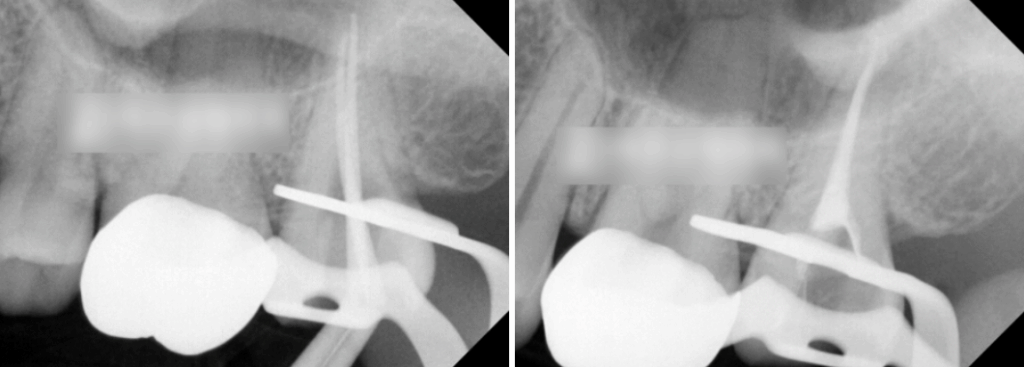

치수 부근까지 감염된 우식

근관 내부 길이를 측정한 다음

썩어 있는 곳들을 깨끗하게 제거합니다.

이후 몇 차례의 제거, 소독과정을 거친 후

확실하게 제거된 것을 확인한 뒤

충전재를 이용하여 뿌리 끝까지 밀폐를 시킵니다.

위쪽 맨 안쪽에 위치한 어금니라

기구의 접근도 쉽지 않을 것으로 예상됩니다.